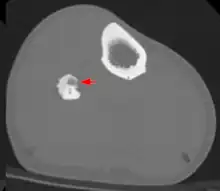

CT scan showing an osteoid osteoma of the fibula with a clearly visible nidus

Radiographs in osteoid osteoma typically show a round lucency, containing a dense sclerotic central nidus (the characteristic lesion in this kind of tumor) surrounded by sclerotic bone. The nidus is seldom larger than 1.5 cm.

The lesion can in most cases be detected on CT scan, bone scans and angiograms. Plain radiographs are not always diagnostic. MRI adds little to the CT findings which are useful for localisation. Radionuclide scanning shows intense uptake which is useful for localisation at surgery using a hand held detector, and for confirmation that the entire lesion has been removed.[8][9]